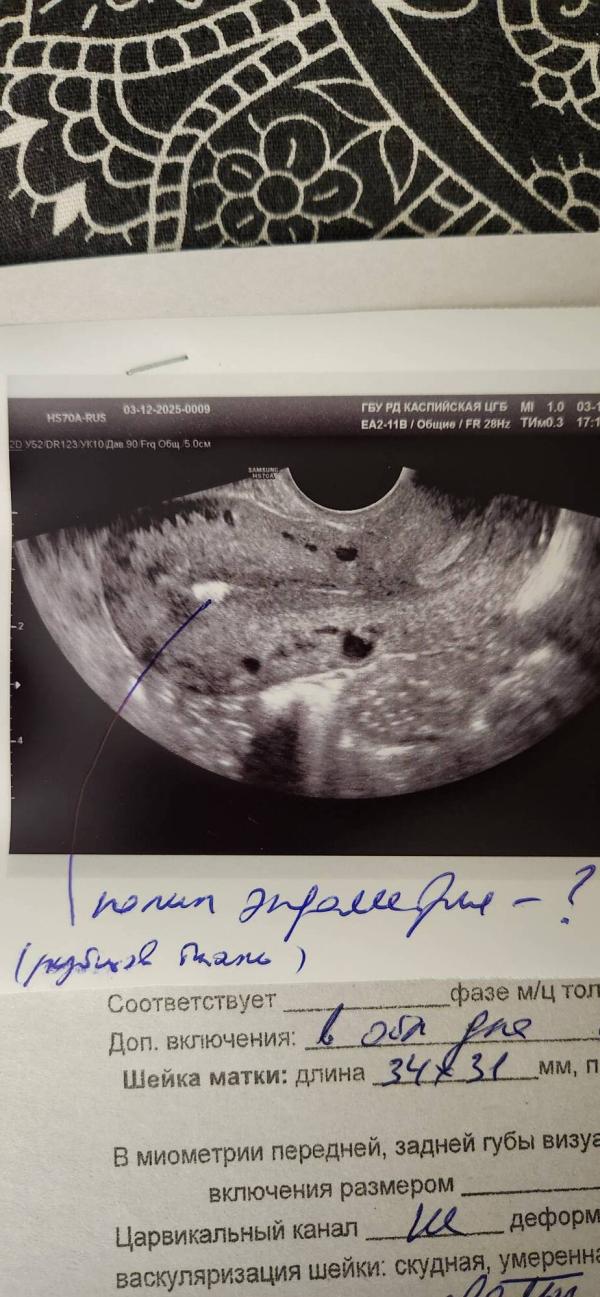

После родов впервые пошла на узи

Сказали в матке что-то есть. Направили на экспертное узи. Записалась к Муминат, но терпения не хвататет, думаю об этом

Врач сказала не полип, но поставила вопрос, потому что сама не поняла что это

(Еще предположила рубец, но никаких вмешательств во время и после родов не было )